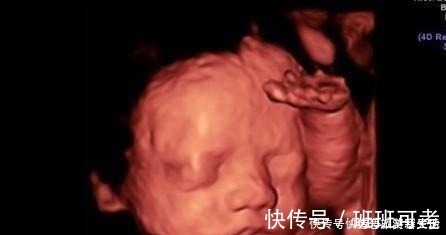

1.实时观察胎儿动态运动,检查胎儿生长发育情况。在怀孕期间,孕妈妈可以通过四维彩超得知胎儿在宫内的一些动态情况。比如说,通过四维彩超能够清楚的看到胎儿在宫内吞吐羊水,眨眼睛,吮吸手指,做鬼脸等动作。医生还可以通过四维彩超更清楚的看得到胎儿的发育情况,比如说血管畸形,体表畸形,内脏畸形等等,提前得知胎儿是否有唇裂,脊柱裂,骨骼发育不良,先天性心脏病等疾病,做到早知道早干预早治疗。2.图像清晰逼真。四维彩超相对于三维彩超更高清更精确,所以看起来更清晰,很多孕妈妈在做四维的时候就可以清晰地看到胎儿的五官,可以初步的判断一下胎儿到底长得像准爸爸还是准妈妈,所以,四维彩超也成为胎儿人生中的第一张照片。而不像二维一样,在大部分人看来就是黑坨坨的一片。

3.没有辐射。在怀孕期间孕妈妈是非常害怕辐射的,担心会对胎儿不利,但是四维彩超也是b超的一种,属于超声波,声波,是没有辐射的。就算孕妈妈在怀孕期间经常做b超也不需要担心会对胎儿造成影响。懒妈妈这边没有四维,怀孕的时候做的只是三维,但是做完三维之后也可以很清楚的看到胎儿的鼻子,眼睛,嘴巴,下巴等,和二维简直是不同一个概念。如果和四维相比,三维就又差得远了。